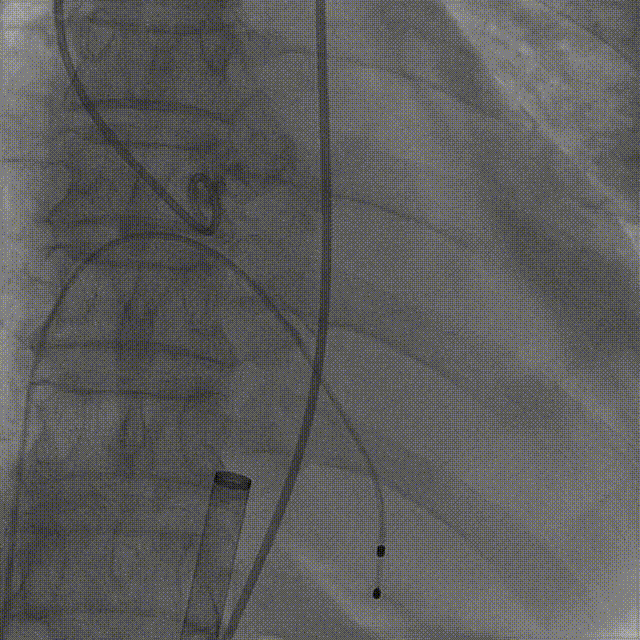

1.根据术前测量分析,采取右侧股动脉作为主入路,左股为辅入路,冠脉造影显示双侧冠脉灌注良好。

左冠造影

右冠造影

2.置入猪尾进行根部造影,造影可见主动脉根部大量钙化,瓣叶活动度低,冠脉灌注良好,中量反流。

根部造影